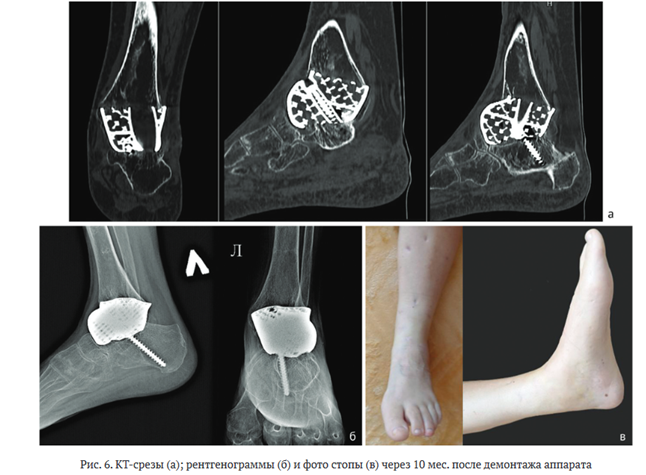

На контрольном осмотре через 10 мес. клинически и рентгенологически ранней нестабильности компонентов эндопротеза и ^-пористого титанового имплантата не наблюдали (рис. 6). Пациентка ходит без использования средств дополнительной опоры в ортопедической диабетической обуви с индивидуальными ортопедическими стельками.